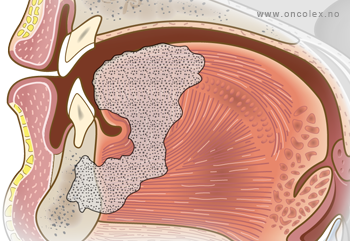

T4: Omfattende svulster med innvekst i naboorgan, muskulatur, skjelett og hud.

- T4 – omfattende svulster med innvekst i naboorgan, muskulatur, skjelett og hud